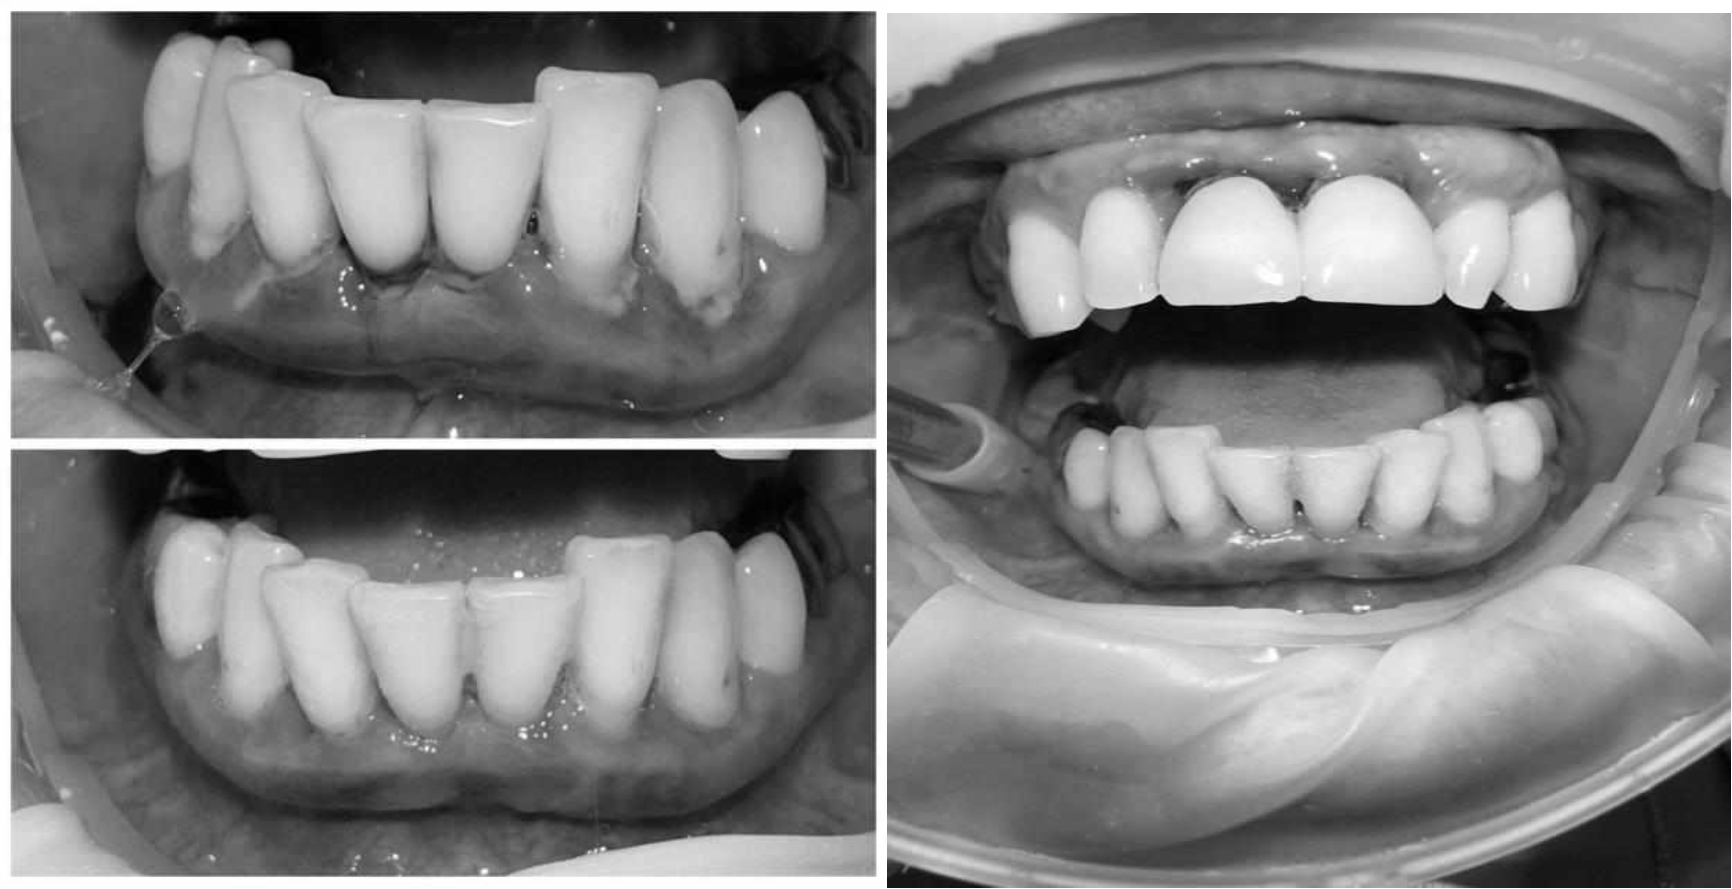

Ранее у пародонтолога не наблюдалась. При осмотре выявлены: неудовлетворительная индивидуальная гигиена полости рта, пародонтальные карманы до 7 мм, обильная кровоточивость и гноетечение из пародонтальных карманов, подвижность зубов 4.2, 4.1, 3.1, 3.2 II степени, обильные над- и поддесневые зубные отложения (рис. 1). На ортопантомограме отмечается резорбция костной ткани до ½ длины корня, очаги остеопороза (рис. 2). Пациенту был поставлен диагноз хронический генерализованный пародонтит тяжелой степени тяжести. При осмотре была составлена пародонтограмма с использованием компьютерного зондирования (рис. 3).

Рис. 2. Ортопантомограмма исходной ситуации пациента  состояния полости рта

Через 6 месяцев при осмотре выявлен удовлетворительный уровень индивидуальной гигиены, отсутствие участков кровоточивости и гноетечения (рис. 4), пародонтальные карманы уменьшились в размерах (рис. 5). Пациент отмечает значительные улучшения. После стабилизации пародонтологического статуса пациент направлен для дальнейшего ортопедического лечения.

Рис. 4. Динамика результата через 6 месяцев